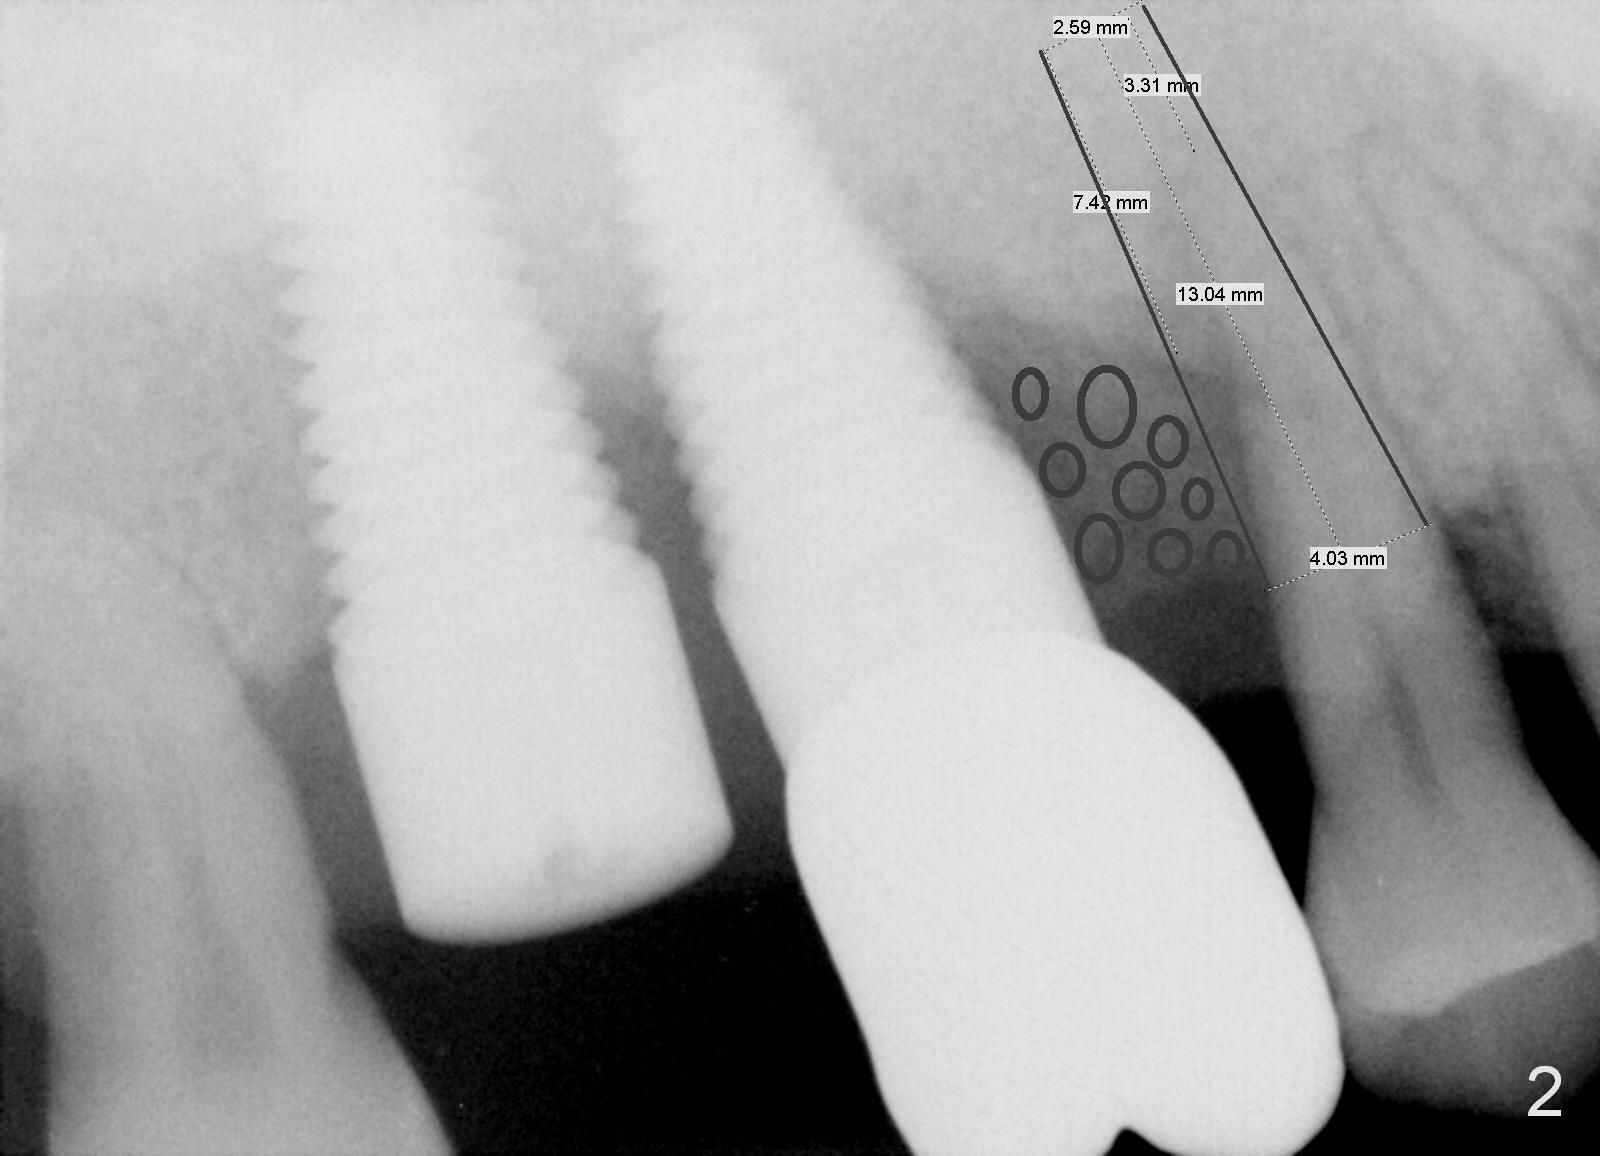

A 46-year-old man has severe chronic periodontitis associated with bruxism. The teeth #3 and 2 have been replaced with immediate implants (Fig.1,2). Now the tooth 4 should be treated in the same manner. Since there is sufficient bone with uneven bone resorption, a long bone-level implant is needed for primary stability (>13 mm). Cuff length of the tissue-level implant is fixed, while there are different lengths of the cuff associated with bone-level implants. Metronidazole is the antibiotic to be used for socket disinfection. Intraop PA should be taken with the pilot drill or a parallel pin to avoid invading the neighboring root or implant. Abundant bone graft is required (circles, Fig.2).